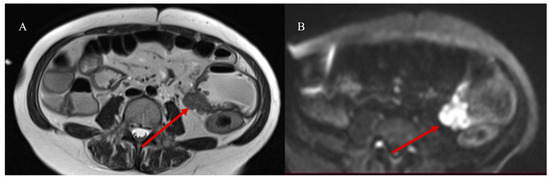

- Masselli, G.; Casciani, E.; Polettini, E.; Laghi, F.; Gualdi, G. Magnetic resonance imaging of small bowel neoplasms. Cancer Imaging 2013, 13, 92–99. [Google Scholar] [CrossRef] [PubMed]

- Faggian, A.; Fracella, M.R.; D’alesio, G.; Alabiso, M.E.; Berritto, D.; Feragalli, B.; Miele, V.; Iasiello, F.; Grassi, R. Small-Bowel Neoplasms: Role of MRI Enteroclysis. Gastroenterol. Res. Pract. 2016, 2016, 9686815. [Google Scholar] [CrossRef]

- Lu, J.; Zhou, Z.; Morelli, J.N.; Yu, H.; Luo, Y.; Hu, X.; Li, Z.; Hu, D.; Shen, Y. A systematic review of technical parameters for MR of the small bowel in non-IBD conditions over the last ten years. Sci. Rep. 2019, 9, 14100. [Google Scholar] [CrossRef]

- Pezzella, M.; Brogna, B.; Romano, A.; Torelli, F.; Esposito, G.; Petrillo, M.; Romano, F.; Di Martino, N.; Reginelli, A.; Grassi, R. Detecting a rare composite small bowel lymphoma by Magnetic Resonance Imaging coincidentally: A case report with radiological, surgical and histopathological features. Int. J. Surg. Case Rep. 2018, 46, 50–55. [Google Scholar] [CrossRef]

| MRI | ||||

| MRE | For SBT tissue characterization in non-emergency cases or in stable patients | Intestinal distension with oral biphasic contrast agents, with an optimal volume of 1000–1500 mL that can be ingested over 45–60 min before the examination; T2 HASTE with and without FS on axial and coronal plane; Trufi T2 on axial and coronal plane; DWI; VIBE T1 FS pre-contrast on coronal plane; if stenosis is present, it may be helpful to use the cine-balanced sequence | Tissue characterization through multiparametric sequence; DWI can be used to predict and monitor SBTs; DWI is more sensitive to detecting LI metastasis in liver steatosis | Claustrophobia; PMK not MRI-compatible |